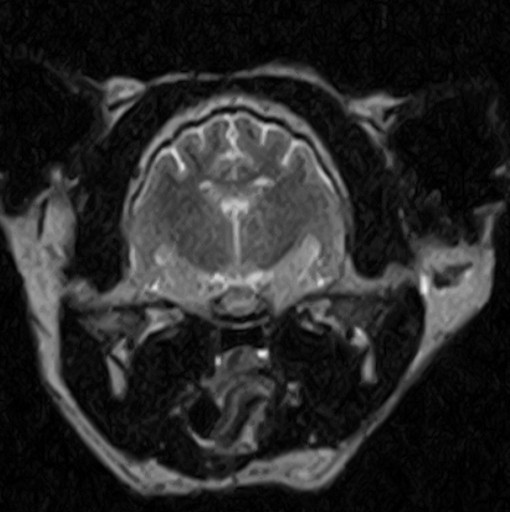

W obrębie mózgowia i trzewioczaszki najczęstszymi wskazaniami do badania MRI są:

• proces nowotworowy

• wodogłowie

• ziarniakowe zapaleniu mózgu i opon mózgowych

• diagnostyka zmian udarowych